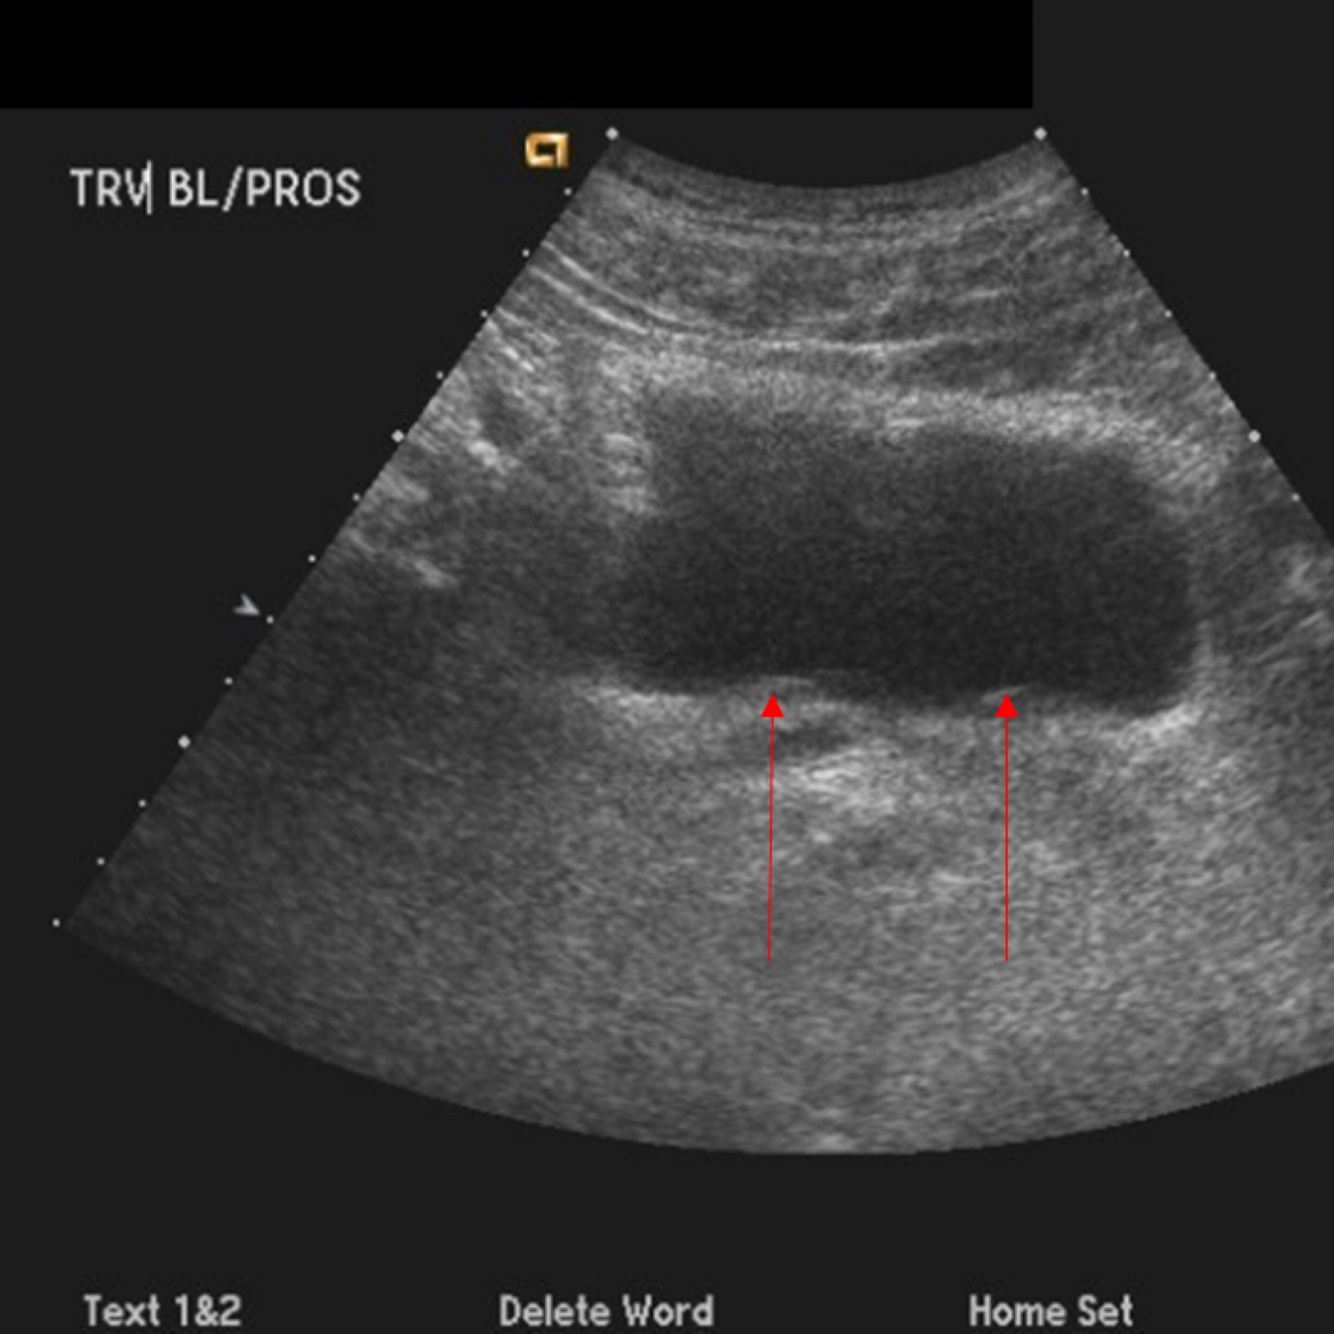

The arrows represent what?

A

The UVJ